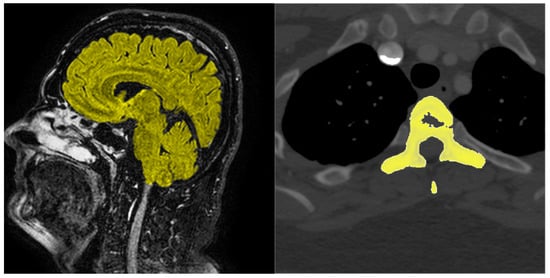

The majority of work in medical image data segmentation focuses on segmenting abnormal tissue regions to determine correct diagnose and the progress of cancer tumours. The problem we are addressing with this paper is the semantic segmentation and subsequent modelling of 3D volumetric segmentations of brain and spine of the patient from MRI and CT scans. Example of MRI and CT scan slices can be seen in Figure 1. Current technology in additive manufacturing and virtual reality brings the doctors new possibilities in examining the patient before operation in high level of detail. To help automate the process of creating accurate 3D models of different parts of human body we propose an optimized neural network architecture evaluated on both MRI and CT images of soft and bone tissue capable of processing data in its original resolution and accelerated on graphical process unit (GPU) for faster parallel computation.

Figure 1.

Example of MRI sagittal brain scan slice (left) and CT transversal thoracic scan slice (right)—tissue segmented with our system is highlighted in yellow.